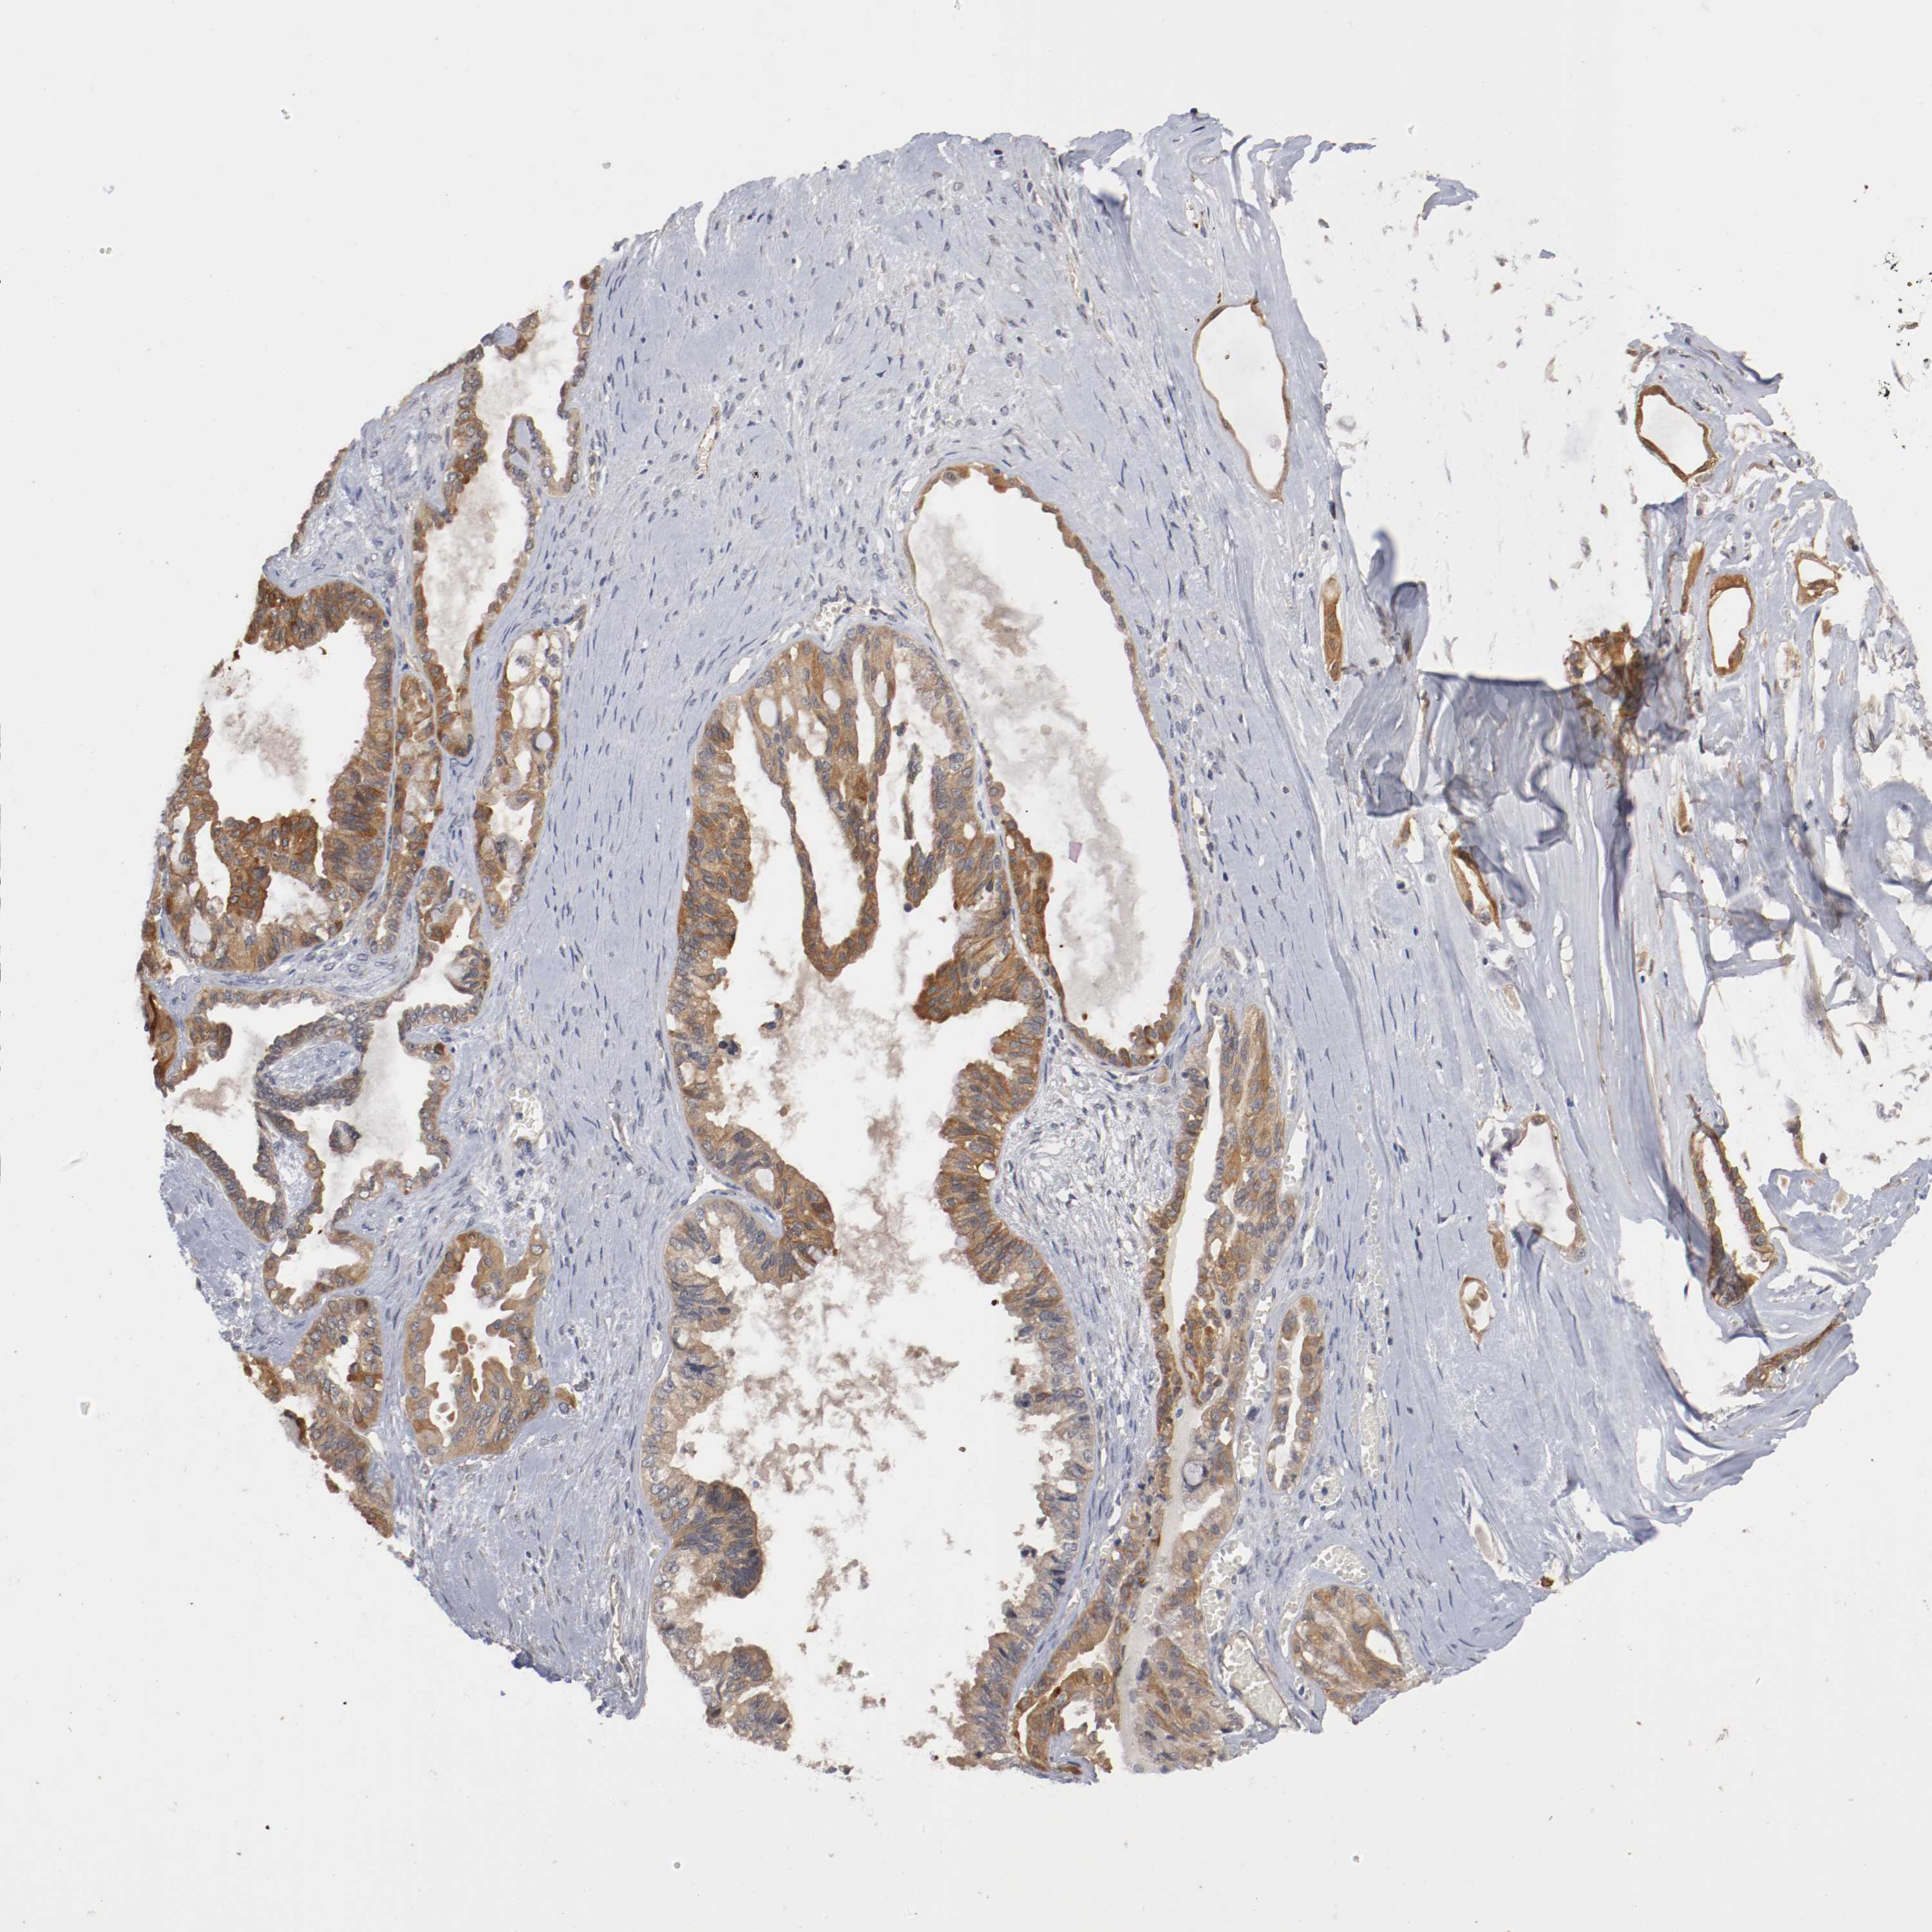

OVARIAN CANCER - Protein expressioni

A mouse-over function shows sample information and annotation data. Click on an image to view it in a full screen mode. Samples can be filtered based on level of antibody staining by selecting one or several of the following categories: high, medium, low and not detected. The assay and annotation is described here.

Note that samples used for immunohistochemistry by the Human Protein Atlas do not correspond to samples in the TCGA dataset.

Antibody stainingi

Antibody staining in the annotated cell types in the current human tissue is reported as not detected, low, medium, or high, based on conventional immunohistochemistry profiling in selected tissues. This score is based on the combination of the staining intensity and fraction of stained cells.

Each image is clickable and will lead to virtual microscopy that enables deeper exploration of all samples and also displays staining intensity scores, fraction scores and subcellular localization as well as patient and tissue information for each sample.

Antibody HPA004144

Staining

High

Medium

Low

Not detected

Intensity

Strong

Moderate

Weak

Negative

Quantity

>75%

75%-25%

<25%

None

Location

Nuclear

Cytoplasmic/membranous

Cytoplasmic/membranous,nuclear

Cystadenocarcinoma, serous, NOS

Carcinoma, endometroid

Carcinoma, NOS

Cystadenocarcinoma, mucinous, NOS